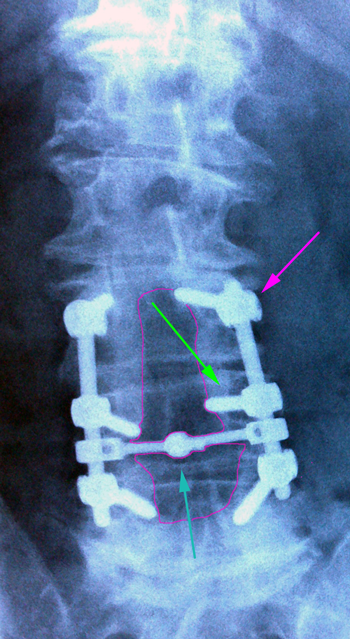

Οσφυϊκή σπονδυλοδεσία Ο3-Ο5. Βίδες στα σώματα των σπονδύλων (πράσινο βέλος) ενωμένες με ράβδους (φούξια βέλος). Συνδετική γέφυρα με κυανό βέλος.Περιοχή της πεταλεκτομής με κόκκινο περίγραμμα.